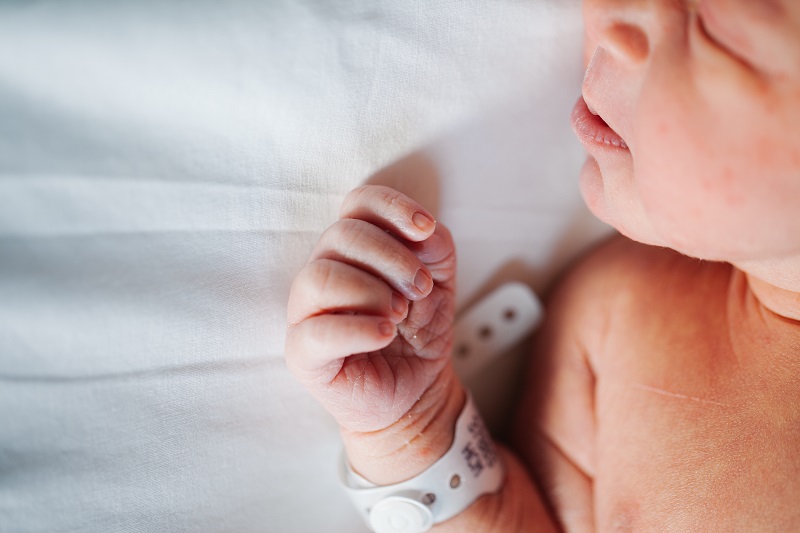

AI-based early detection of cerebral palsy

BulletProve is responsible for the development and implementation of AI algorithms for video analysis and motion pattern detection in infants, in accordance with the Prechtl General Movements Assessment method.

- Computer Vision and Machine Learning applied to infant movement analysis from video recordings

- Detection and segmentation of pathological movement patterns